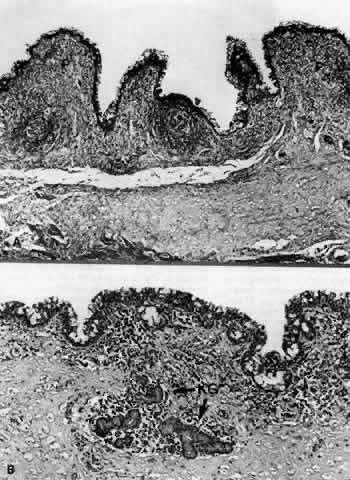

A subconjunctival accumulation of aqueous called a filtering bleb is commonly seen after successful glaucoma filtering surgery. The diameter, elevation, and vascularity of filtering blebs are highly variable. Functioning blebs may be thin and polycystic, or they may have a flatter, thicker, and more diffuse appearance. Nearly all functioning blebs are relatively avascular and contain small cystic spaces (microcysts).86 Microcysts are best seen with indirect illumination and probably represent channels for the passage of aqueous humor. Histologically, functioning blebs show normal conjunctival epithelium with no junctions between the cells that would limit fluid movement. The subepithelial connective tissue is loosely organized and contains many histologically clear spaces. The clear spaces probably correspond to the microcysts seen clinically.103

In failed blebs, the conjunctiva is scarred to the underlying episcleral tissue.87 Failed blebs are typically low to flat and heavily vascularized with no microcysts. Both light and electron microscopy of failed blebs reveals normal epithelium, but abnormally dense and thickened subepithelial connective tissue due to large amounts of collagen. Also, fibroblasts and blood vessels are present in the bleb wall.103 Failed blebs must be differentiated from encapsulated blebs (Tenon's capsule cysts). Encapsulated blebs are smooth, dome-shaped, conjunctival elevations with large vessels separated by avascular spaces. Microcysts are not usually present. Encapsulated blebs trap aqueous over the filtering site, thereby raising intraocular pressure. Unlike failed blebs, however, most of these blebs will recover function within a few months.86 Histologically, encapsulated blebs consist of thin, almost avascular sheets of fibrous connective tissue with areas of proliferating fibroblasts. The inner surfaces of the bleb walls are lined with acellular material (probably fibrin).87